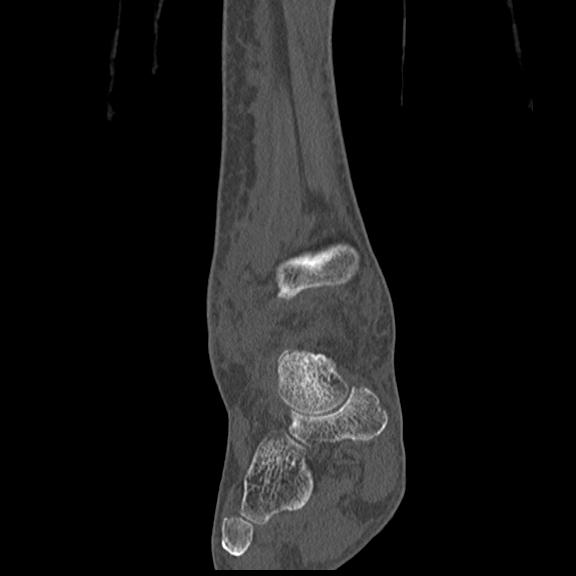

102803 1/12(キウスなし) 1/27 左下腿 4R 30歳女性 左脛骨軸内釘